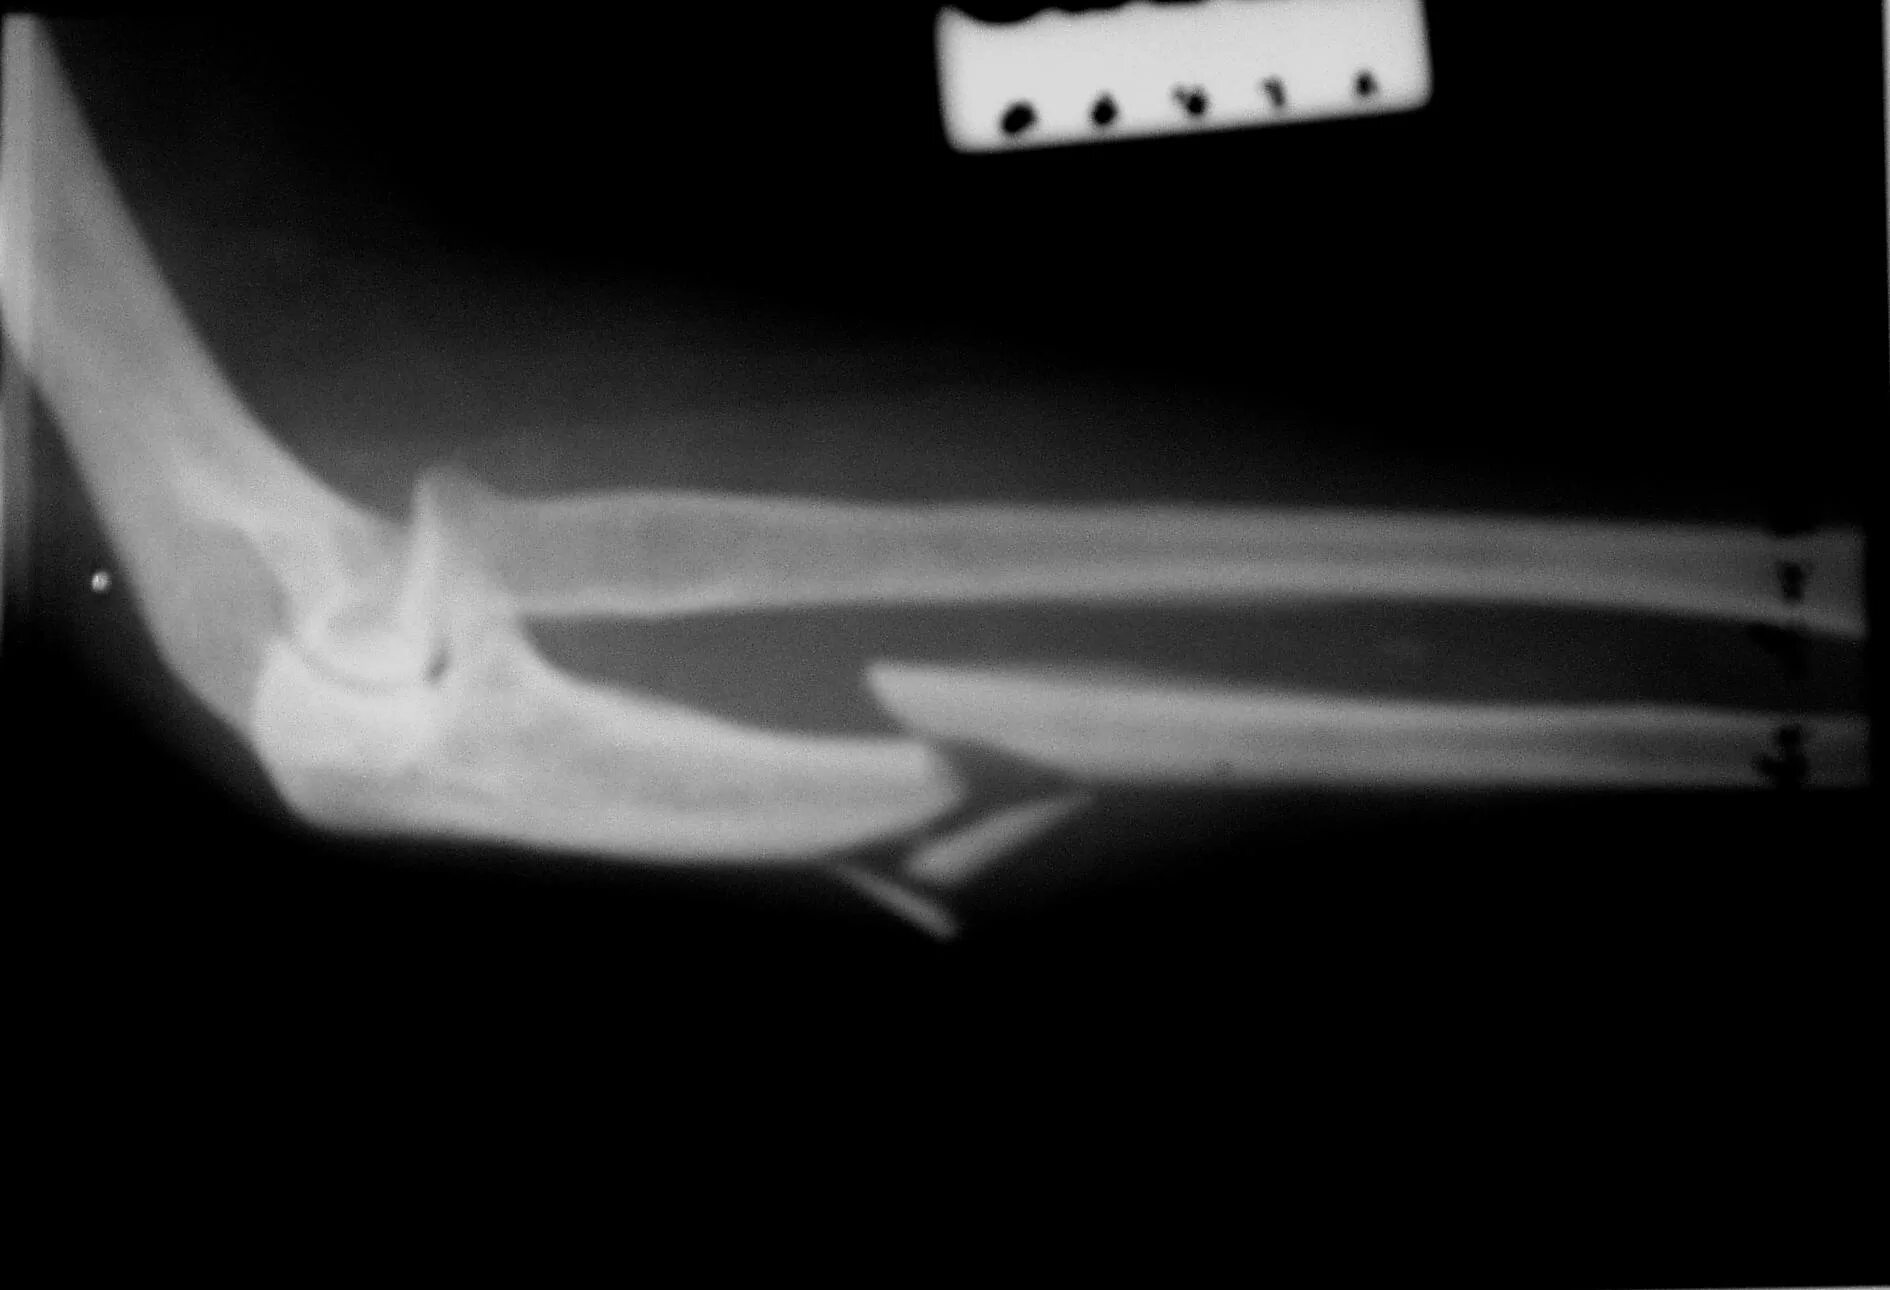

Закрытый оскольчатый перелом со смещением